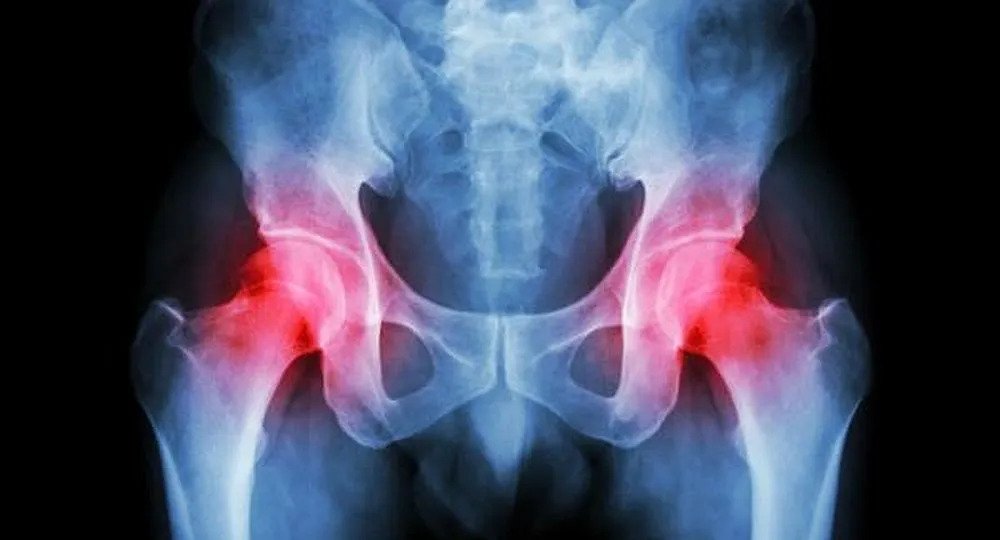

Kalça kemiği çürümesi, tıptaki adıyla avasküler nekroz, kalça eklemindeki kemik dokusunun yeterince kanlanamaması sonucu zamanla burada kemik dokusunda hücre ölümü ve canlılığını kaybetmesi durumudur. Bu hastalık, genellikle femur başı (uyluk kemiği başı) bölgesinde görülür ve tedavi edilmezse ciddi eklem hasarına ve hareket kısıtlılığına yol açabilir.

Kalça Kemiği Çürümesi belirtileri arasında kasık, kalça ya da uylukta ağrı, yürümede zorlanma, hareket kısıtlılığı, merdiven çıkarken ya da çömelirken ağrının artması gibi belirtiler genellikle yavaş yavaş ortaya çıkar ve zamanla şiddetlenir. Hastalık zamanla ilerleyici ve kalça eklemini harap eden bir hal alabilir.